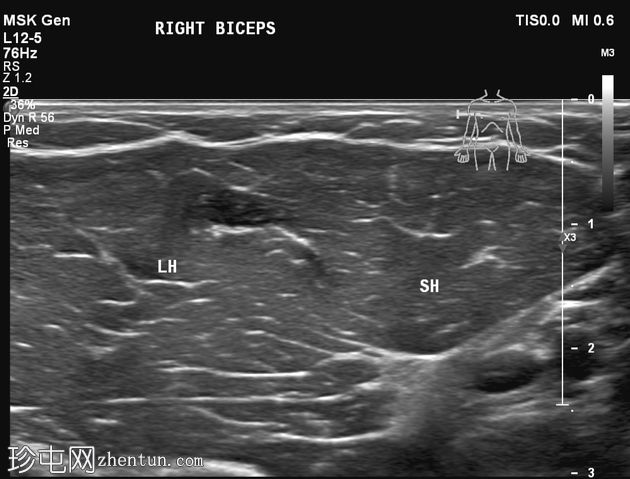

横断面

静息状态:肱二头肌短头和长头肌肉结构正常。肌腱和肌腱连接处完整,仅有轻微的断裂或积液迹象。

肘关节屈曲及肌肉收缩动态成像:肱二头肌短头和长头肌纤维之间出现充满液体的裂隙,提示局部肌筋膜分离/拉伤。未见肌纤维全层撕裂。肱二头肌远端止点正常。

诊断:肱二头肌短头和长头之间的动态肌筋膜损伤,收缩时裂隙内积液。

静息状态下的图像可能显示正常,这凸显了对有症状患​​者进行动态检查的重要性。